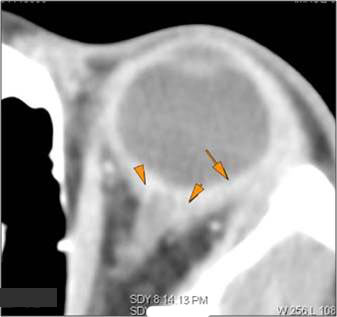

Orbits

The extraconal orbital fat is abnormal. [Yes/No]

There is a subperiosteal abscess or edema along the medial wall, roof or floor of the orbit. [Yes/No]

The extraocular muscles are swollen or otherwise abnormal. [Yes/No]

There is bone erosion along the walls of the orbit. [Yes/No]

The intraconal orbital fat is infiltrated. [Yes/No]

The orbital apex and the superior and inferior orbital fissures are infiltrated. [Yes/No]

The superior and/or inferior ophthalmic veins are dilated or thrombosed. [Yes/No]